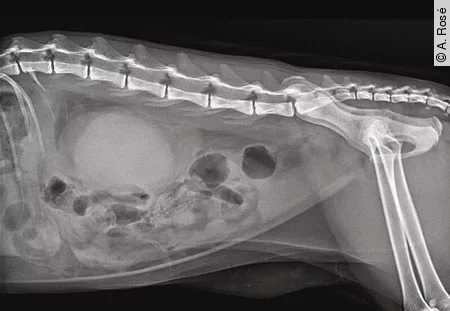

Bildgebende Verfahren wie Abdomen Ultraschall und Röntgen sind unerlässlich, um strukturelle Veränderungen (z. B. Zysten, Neoplasien) zu erkennen und Komplikationen wie Hydronephrose oder Uretersteine zu identifizieren [Abb. 1] und [2]. Weitere spezifische Untersuchungen (z. B. T4, PTH-Bestimmung, SDMA) können je nach klinischem Verdacht ergänzend sinnvoll sein [Tab. 1] und [2].